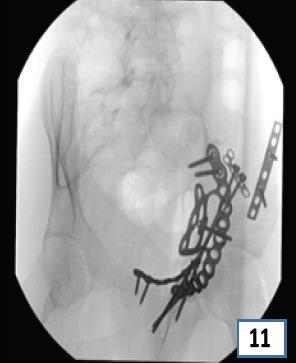

在此,我们报告一例16岁男性,有道路交通事故史,单纯闭合性左髋臼骨折。X线显示双侧髋臼柱骨折伴中心性半脱位。通过改良的Stoppa入路并带有外侧窗口对其进行切开复位内固定治疗。患者在受伤后第6天接受了ORIF。使用钢板和螺钉进行固定。在恢复室,他整个左上肢无法活动且无感觉,而手术肢体的远端神经血管功能正常。恢复15分钟后,感觉恢复,但运动功能障碍持续存在,提示臂丛神经失用。进行了脑部CT扫描,结果未见异常。6个月后,患者自行恢复了感觉,左上肢力量改善至5/5。